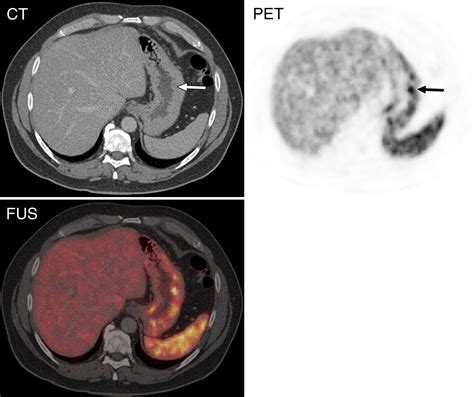

A Dotatate PET scan—often formally referred to as a Gallium-68 (Ga-68) DOTATATE PET/CT scan—is a sophisticated type of molecular imaging. Unlike conventional scans like CT or MRI, which primarily look at the size and shape of body structures, a PET scan focuses on how cells function at a molecular level.

The "Dotatate" component is a radioactive pharmaceutical agent. It acts as a targeted seeking device that binds to somatostatin receptors. These receptors are often found in high concentrations on the surface of neuroendocrine tumor cells. Because these tumors "light up" when the tracer binds to them, the PET scan creates a vivid map of where these tumors are located throughout the body, even those that are too small to be detected by standard imaging.

To understand the superiority of the Dotatate PET scan in this specific context, it is helpful to compare it with other common diagnostic tools.

Imaging Type Primary Strength Limitations for NETs

Standard CT Scan Excellent anatomical detail. May miss very small tumors or differentiate between scar tissue and tumors.

MRI Great for soft tissue detail. Can be time-consuming; less sensitive to systemic disease spread.

Dotatate PET Scan High molecular sensitivity. Specific to tumors with somatostatin receptors.

Once the scan is complete, the images are sent to a radiologist or nuclear medicine physician who specializes in interpreting these complex studies. They will analyze the images to identify areas of high tracer uptake, which indicate the presence of neuroendocrine tumor cells. The results are typically combined with findings from other tests and your clinical history to provide a comprehensive summary of your condition.